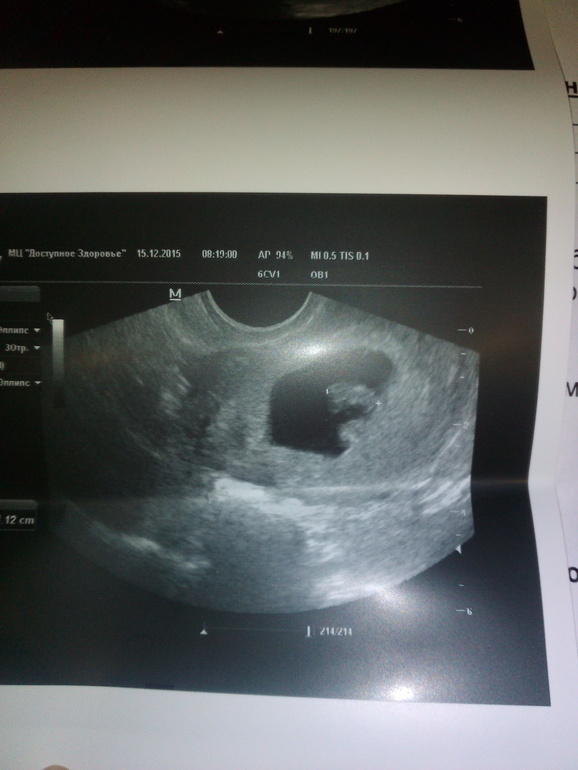

УЗИ, КТГ, доплерДевочки сегодня я услышала самый замечательный неповторимый и самый любимый звук на свете ЭТОТ ЗВУК.....БЬЮЩЕГОСЯ СЕРДЦА МОЕГО РЕБЁНКА)))))) Я ЛЕТАЮ И ЛЮБЛЮ ВЕСЬ МИР СЕГОДНЯ! Целый день улыбка не сходит с моего лица даже скулы болят уже)))) мой маленький кусочек самого большого счастья на свете ЖИВ!!! И РАСТЁТ))) все мои дурацкие тревоги сегодня просто исчезли!!!! Это чудо!!!! Как такое может быть????!!!! Как из простите капельки может такое случится??????? Природа - пипец какая загадочная!! Я такая счастливая!!!!!! Знакомьтесь девочки моё счастье)))